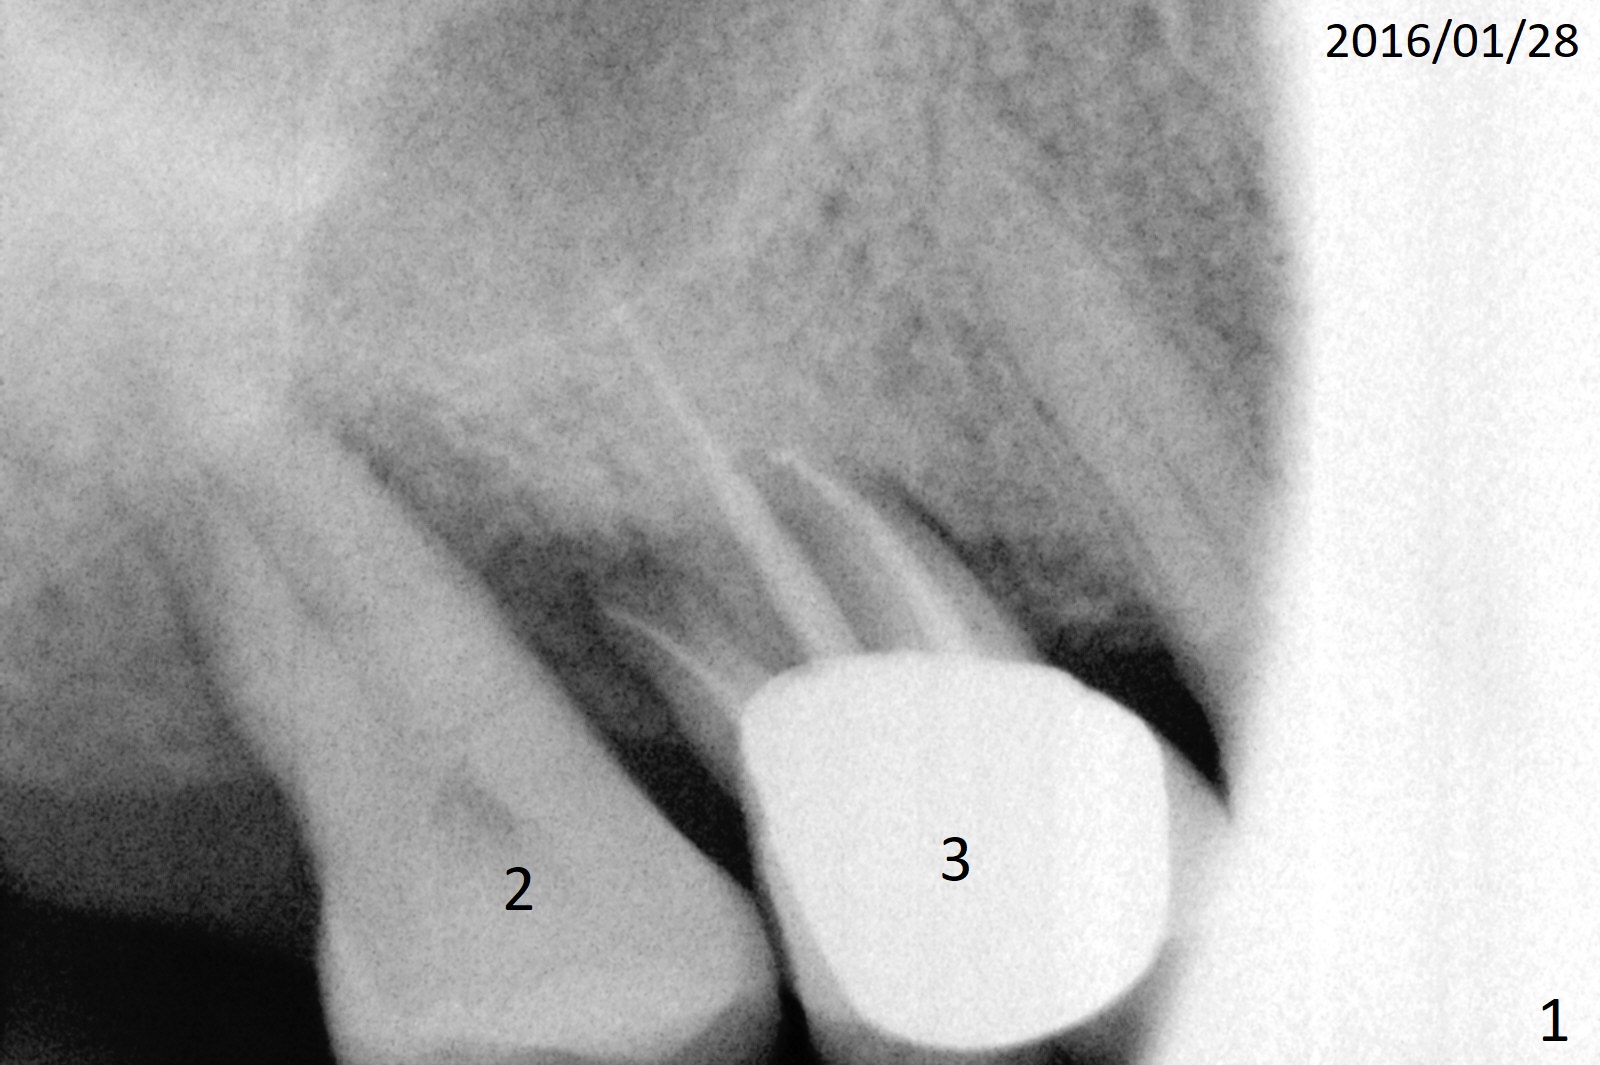

A 66-year-old woman is a bruxer/grinder. She loves chewing bone and eating nuts. The tooth #2 has exfoliated on its own, while the tooth #3 had periradicular bone loss (Fig.1). The upper left FPD is loose because of root fracture at #13 (Fig.2 >). Note the long alveolus. The mesial root of the tooth #30 has been fractured with severe bone resorption for the last 34 months (Fig.3). After extraction, initiate osteotomy in the middle of the socket irrelevant of the septum (Fig.4 red line). Take a PA or panoramic X-ray with a parallel pin immediately. When drills approaches the septum, use Magic Expanders to push the septum distal prior to resuming drills so that a 4.5x13 mm implant (Fig.5 green) is supported by the distally-displaced septum (arrow). The small implant is chosen so that there is room for bone graft, since the buccal and/or lingual plates are most likely defective mesially.